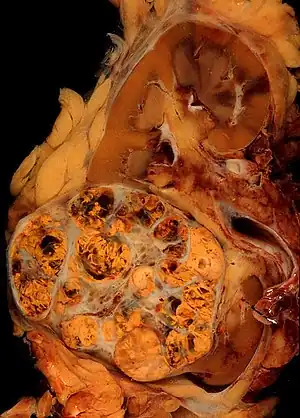

_Nephrectomy.jpg.webp)

- Carcinoma de células renais (90% dos casos)

- Carcinoma de células claras (60 a 80% dos casos): Genético e mais comum em homens com mais de 60 anos. Podem ser classificados em crescimento lento (grau 1) até crescimento rápido (grau 4).